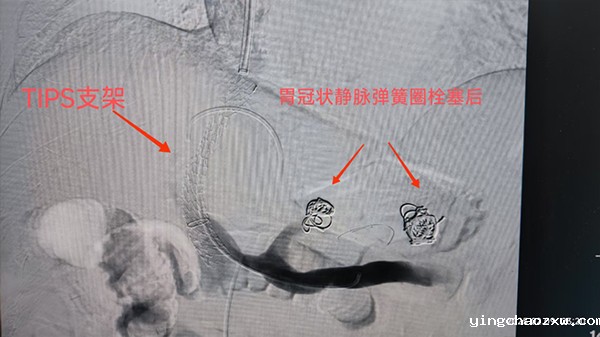

据悉,患者为男性,现年53岁,因“腹痛6小时,呕吐咖啡渣样物4小时”入住北院区消化内科,入院后诊断:1.肝硬化伴食管胃底静脉曲张破裂出血;2.贫血待分度;3.2型糖尿病;4.脾大;5.门静脉高压。急查血常规及血生化后提示:患者白细胞计数:2.69×*10^9/L↓,红细胞计数:2.72×*10^12/L↓,血红蛋白:56.00g/L↓,红细胞比容:0.19L/L↓,血小板计数:38.00×*10^9/L↓,均低于正常值,ABO血型(正、反定型):A型,Rh血型鉴定:阳性。血生化:白蛋白:26.6g/L↓,低于正常值。尿酸:117μmol/L↓,低密度脂蛋白胆固醇:0.91mmol/L↓。鉴于患者病情危重,消化内科给予患者输血、抑制胃酸分泌、降低内脏血管压力、止血、补液、维持电解质平衡等多项治疗,但治疗效果不明显。因肝硬化伴食管胃底静脉曲张破裂出血随时会危及患者生命安全,对其实施经颈静脉肝内门体静脉分流术才能减轻门静脉压力,并控制食管胃底静脉曲导致的消化道出血,于是消化内科遂将其转入肿瘤科。肿瘤科医疗团队积极研讨患者病情,经过审慎认真的评估,决定为其实施经颈静脉肝内门体静脉分流术。手术开展期间,云南大学附属医院曾俊仁教授亲临指导,肿瘤科医疗团队在患者颈部皮肤上开了一个3mm的穿刺点后,采用导丝和导管将支架置入到肝内门静脉与肝静脉之间,建立分流通道,减轻患者门静脉压力。同时,对患者实施胃冠状静脉栓塞术治疗其食管胃底静脉曲张,达到止血效果。术中患者处于清醒状态,无明显不适症状,手术非常成功。后经肿瘤科护理团队精心照顾,患者恢复良好,未出现便血、肝性脑病等并发症,现已顺利出院。

术中造影

术后造影